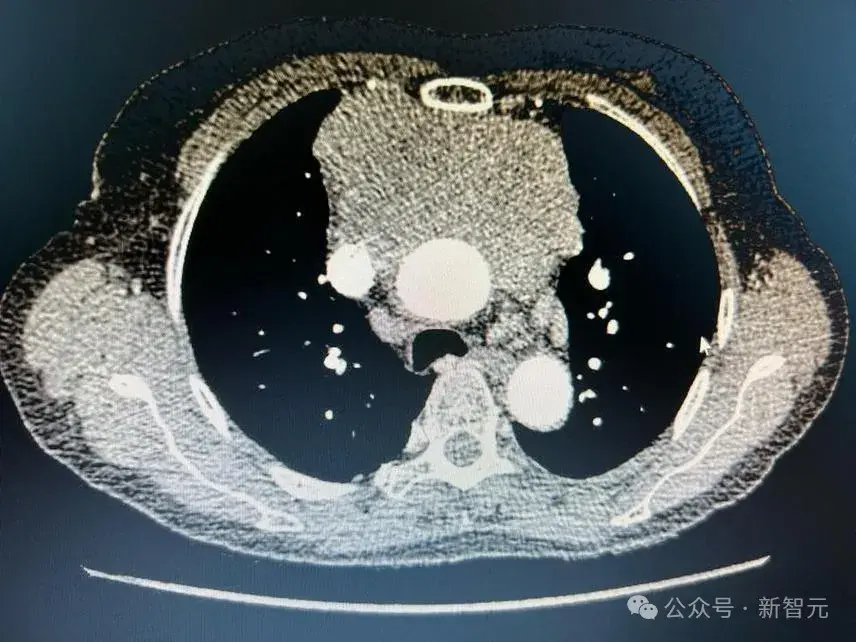

模型注意力得分的可视化显示,CHIEF准确识别了黑色素瘤、肺癌和肾癌的癌变区域

模型注意力的可视化显示了肺癌患者生存预测中的重要区域